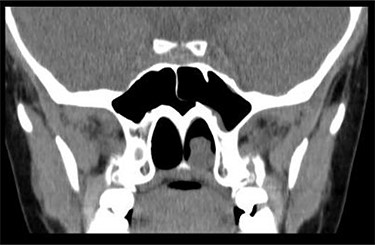

Anterior rhinoscopy revealed hypertrophied inferior turbinates with allergic nasal mucosa and increased nasal secretions with no mass seen. There was no active pus discharge from the nose. On throat examination, a large red, strawberry shaped mass was seen hanging posteriorly in the oropharynx. Flexible nasal endoscopy (FNE) of the left nostril was done, revealing a large polyp extending from the middle meatus into the choana and a clear right airway. A computerized tomography (CT) scan was done (Figs 1 and 2) showing a soft tissue mass arising from the left middle meatus, extending posteriorly and reaching the left choana (Fig. 2).

CT scan—coronal cut showing a homogenous mass occupying the inferior aspect of the left choana.